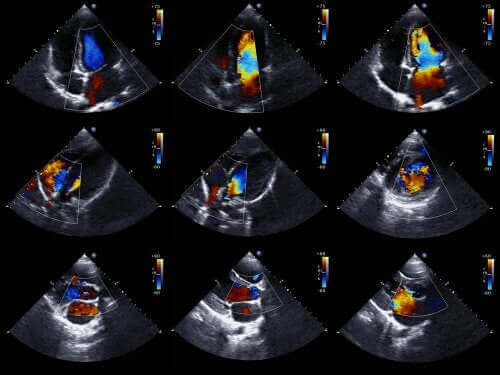

Ekokardiogram är en av de mest effektiva teknikerna för att diagnostisera medfödda hjärtproblem.

Läkare kan vanligtvis diagnostisera denna typ av anomali innan bebisen fötts. För att göra det använder man ett ekokardiogram, som är en teknik med ljudvågor för att skapa rörliga hjärtbilder.

Tack vare detta kan de se hur hjärtat ser ut och undersöka dessa funktion när bebisen fortfarande är i livmodern. Med denna information kan läkarna planera behandlingen och påbörja den direkt efter födseln.